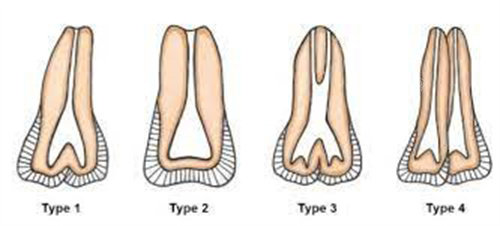

一、种植牙价格参考

作为诊所核心项目,2025 年种植牙价格覆盖不同品牌与需求,所有套餐均包含术前基础检查(口腔 CT、牙周评估)及术后 1 次复查:

韩国登腾(基础款):3980 元起(适合单颗缺牙、预算有限人群,使用寿命 8-10 年)

美国皓圣(中端款):5680 元起(含即刻种植技术,拔牙后可当天种牙,减少就诊次数)

德国 ICX(高端款):7980 元起(钛合金材质,生物相容性强,适合牙周条件较弱人群)

瑞士 ITI(旗舰款):9800 元起(含骨粉补充服务,针对牙槽骨较薄患者,使用寿命 15 年以上)